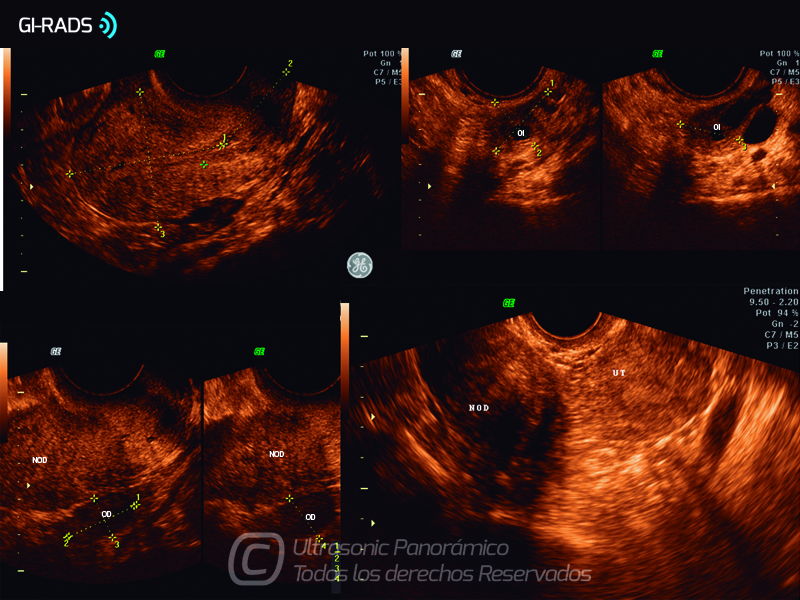

Patologías Benignas – Mioma Pediculado